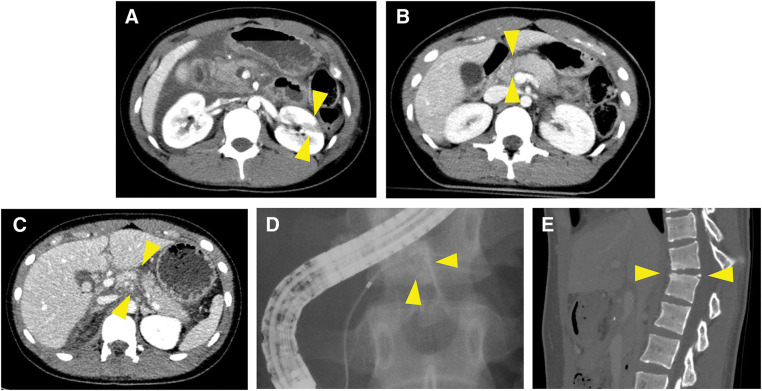

Case presentation: We report 2 cases of young patients with MPD injuries from blunt trauma, both presenting late with significant peripancreatic contamination. Case 1 included a 22-year-old male who sustained pancreatic and liver injuries while skiing. He was transferred 30 hours post-injury with stable hemodynamics. Endoscopic retrograde pancreatography (ERP) confirmed MPD disruption. Intraoperatively, saponification obscured the anatomical structures, but MP with PJ was successfully performed. The patient recovered without major complications. Case 2 involved a 17-year-old female who was initially observed at another hospital after a traffic accident. Three days later, she developed peritonitis, and a retrospective computed tomography review revealed a pancreatic body rupture. An ERP confirmed MPD disruption. During surgery, extensive inflammation and adhesions were noted, and the MPD was extremely small. Despite technical complexities, an MP with PJ was successfully completed. The pancreatic fistula from the pancreatic head stump required drainage treatment following spinal surgery for vertebral fractures, and the patient recovered without sequelae.